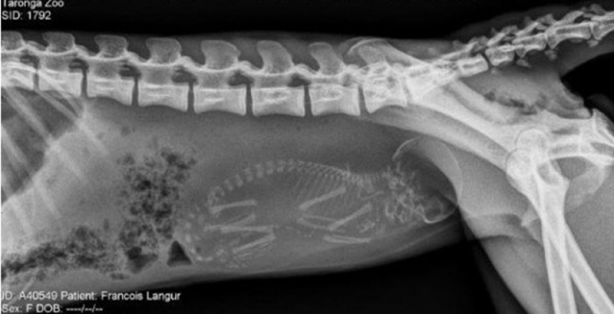

Hamile bir kaplumbağanın röntgen filmi.

Hamile maymun